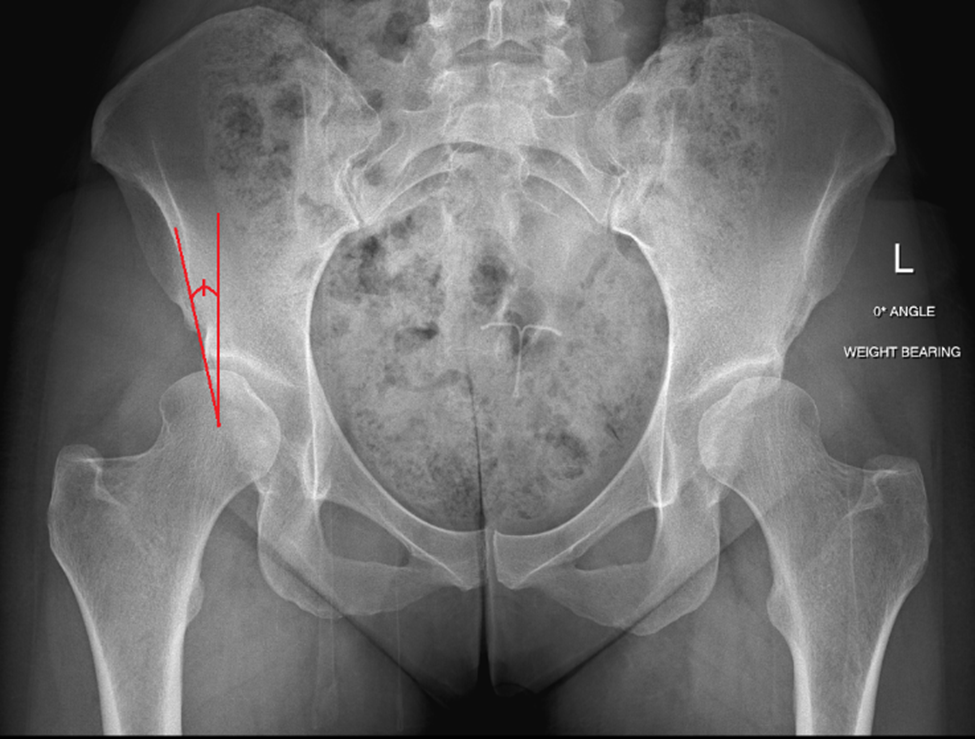

Lateral Center Edge Angle (LCEA)

This is the most commonly measured angle to determine if a person has hip dysplasia. It measures how well the acetabulum (“hip socket”) covers the head of the femur (“ball” of the hip joint).

Normal values are between 25-35 degrees

< 20-25 degrees = hip dysplasia (shallow hip socket)

> 39 degrees = over-coverage of the acetabulum and is associated with pincer impingements in femoral acetabular impingement (FAI)